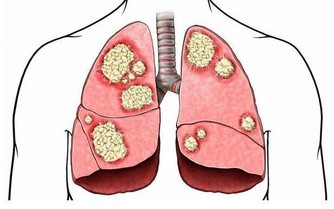

03.不要盲目吃維生素,提醒:這4種維生素若過量服用,或會引起中毒

維生素A

維生素A又名視黃醇,可以抗干眼病因子,

維生素C

維生素C是我們大家都比較熟悉是一種維生素,它參與羥化反應,也有某些藥物代謝有著密切的關係。對於成年人來說,

但是維生素C服用過量仍可產生一些不良反應,

維生素B族

維生素B族過量攝入導致人們出現

一般來說,維生素B過量也會產生毒性反應,引起過敏性休克。如果脂溶性維生素超標,

維生素E

維生素E常用劑型為片劑、膠囊劑、注射劑,一般用於棘紅細胞增多症或吸收不良綜合徵,還用

長期大量使用(每日量400-800mg)